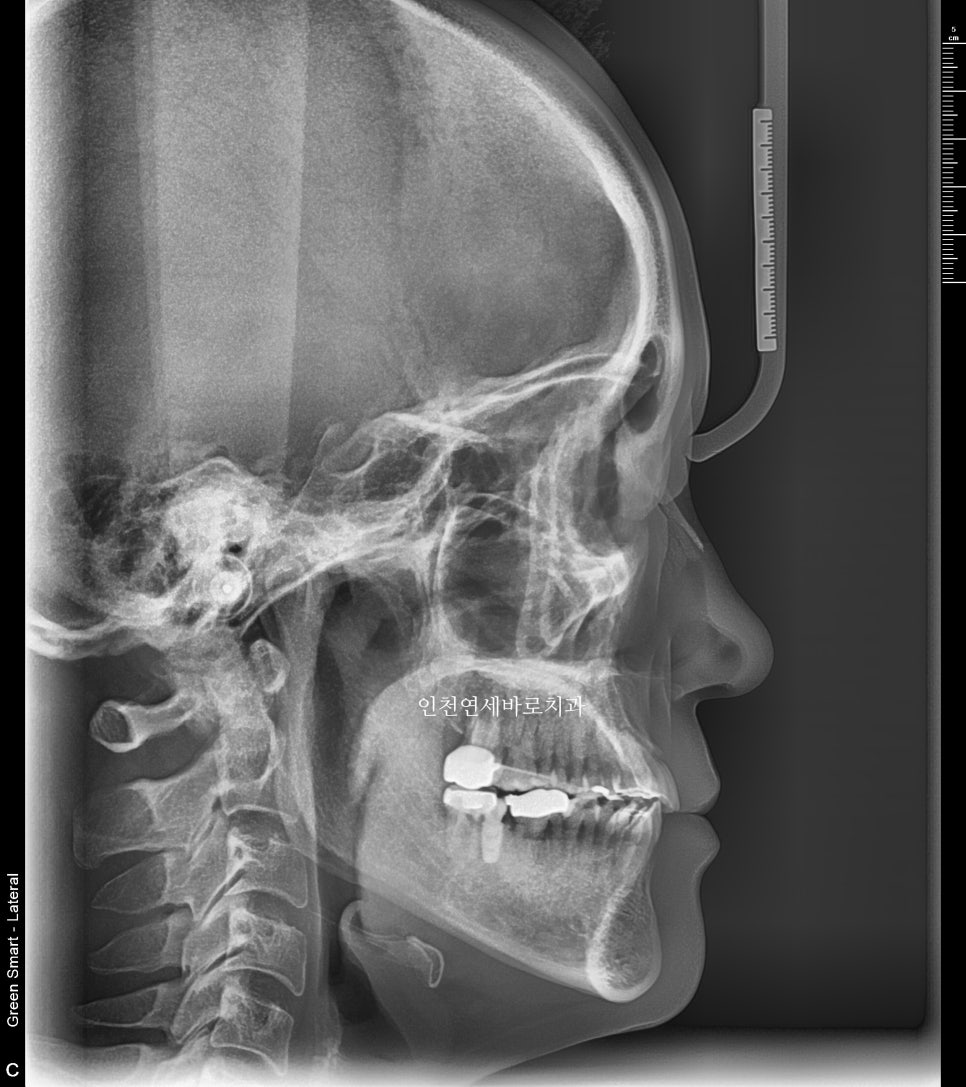

방사선 사진 비교

전후 엑스레이입니다

양악수술은 아니기에 큰 변화는 아니지만 안모의 개선을 확인 가능할겁니다.

양악수술을 하였다면 안모개선 효과가 더 많았겠지만 진단 기준에 따라 수술 없이 주걱턱 교정이 가능함을 보여드리는 포스팅입니다.